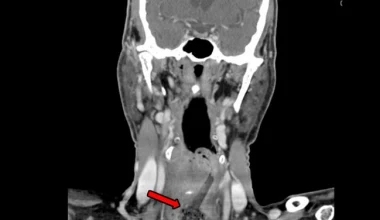

Zlokalizowane ciało obce /Fot. Elsevier

GeekExtra

Zjadł babeczkę z plastikową formą